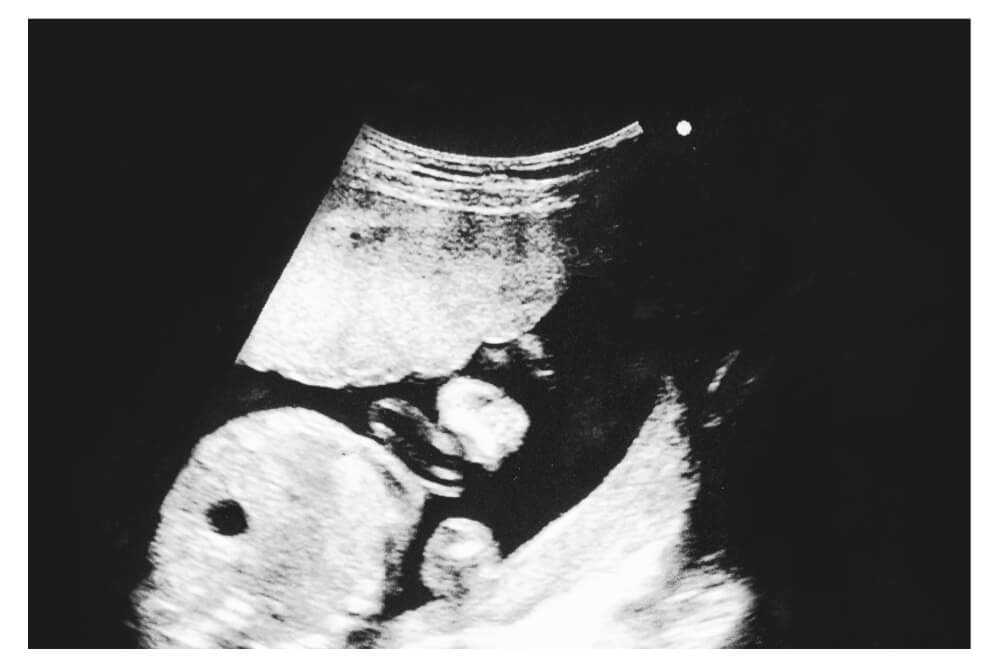

21 Haftalık Gebelikte Ultrason Görüntüsü Nasıl Olur?

- haftada yapılan ultrason, gebeliğin en keyifli ve aynı zamanda en bilgilendirici dönemlerinden biridir. Bebeğin organları artık büyük ölçüde oluşmuştur, kemik yapısı netleşmiştir ve hareketleri ultrason ekranında açıkça izlenebilir. Bu haftada genellikle detaylı ultrason (anomali taraması) yapılır; bu, bebeğin gelişimini adım adım değerlendiren önemli bir incelemedir.

Ultrasonda Görülebilen Detaylar

- haftada ultrason görüntüsünde artık bebeğin yüz hatları, parmakları, el ve ayak tırnakları net bir şekilde görülür.

- Bebeğin kalp atışları dakikada 140–160 aralığında ritmik olarak izlenir.

- Mide ve mesane doluluğu görülebilir; bu da sindirim ve boşaltım sistemlerinin aktif olduğunu gösterir.

- Akciğerler henüz olgunlaşmamış olsa da göğüs kafesinin ritmik hareketleri solunum egzersizlerine işaret eder.

Ultrasonda Görülen Görsel Netlik

Bu haftada yapılan ultrason genellikle 2 boyutlu (2D) olarak gerçekleştirilir. Ancak bazı merkezlerde 3D veya 4D ultrason teknolojileriyle bebeğin yüzü, el hareketleri ve mimikleri daha net izlenebilir.

- 3D ultrason: Yüz ve vücut hatları belirgindir.

- 4D ultrason: Bebeğin hareketleri gerçek zamanlı olarak izlenebilir.